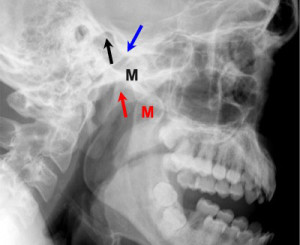

Провести диагностику можно при внешнем осмотре, главное, отличить его от перелома. Для этого необходимо проведение рентгенологического обследования. Пациент и его окружение не должны пытаться самостоятельно вправить вывих нижней челюсти, поэтому следует как можно быстрее обратиться к врачу. Только он может произвести вправление и назначить необходимее лечение.

Присутствие вывиха врач может подтвердить при помощи рентгена. Сразу после подтверждения диагноза производится вправление челюсти. Проводят данное лечение под местной анестезией.